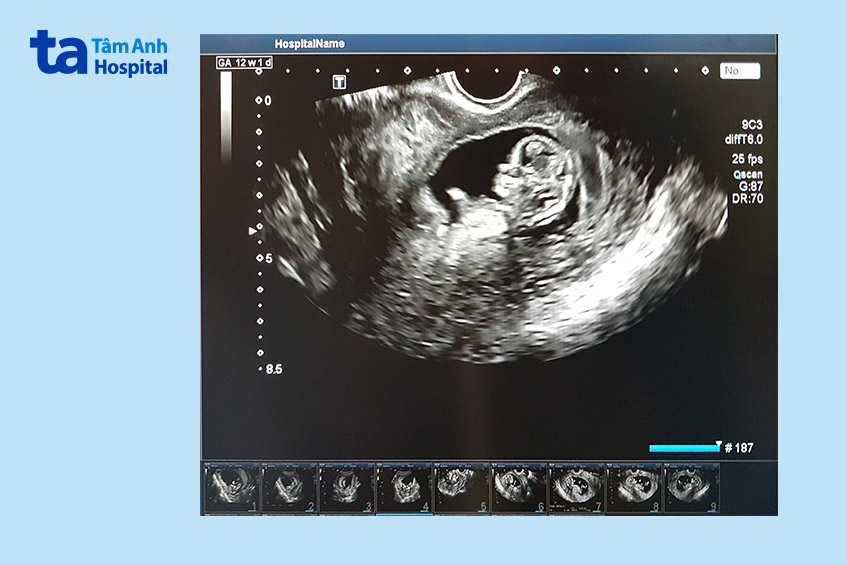

Trên siêu âm, thai IVF 12 tuần có hình dạng và kích thước như sau:

Hình ảnh siêu âm cung cấp thông tin chi tiết về sự phát triển của thai IVF 12 tuần, giúp bác sĩ theo dõi sát sao tình trạng của mẹ và bé.